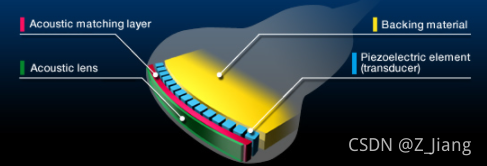

超声探头本身包含数以百计的element,我们在发射声波时可以逐个控制阵元的发射延时和电压,从而控制声场。概念上,波束合成包含两部分,一个是发射,另一个是接收;

Func_tx是发射部分,它直接决定了声场的情况。我仿真了一组声场,我们先直观的感受一下,声压在组织中的传播所形成的声场,见下面的视频

这组仿真,是一个64阵元的小探头(按常规的相控阵配置的),声场区域长宽都是4厘米,发射聚焦在2厘米的深度,2个Cycle的激励,2MHz的发射频率。实际上声场本身是机械波的传播过程,在传播过程中会与组织发生交互,在各个位置上不断发生反射,折射,散射,衍射。上面大家看到的声场中,没有任何反射等交互,是因为我们仿真的是在水中传播的情况,没有任何的物质。但我们可以看到,由于控制了发射延迟,让所有的阵元的声波同时到达2厘米处,在2厘米处波束很窄很集中,在焦点前后逐渐远离发射焦点的地方,波束逐渐变宽。